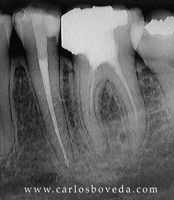

Video de un Retratamiento de Conductos en Una Sesión - (formato Quicktime)